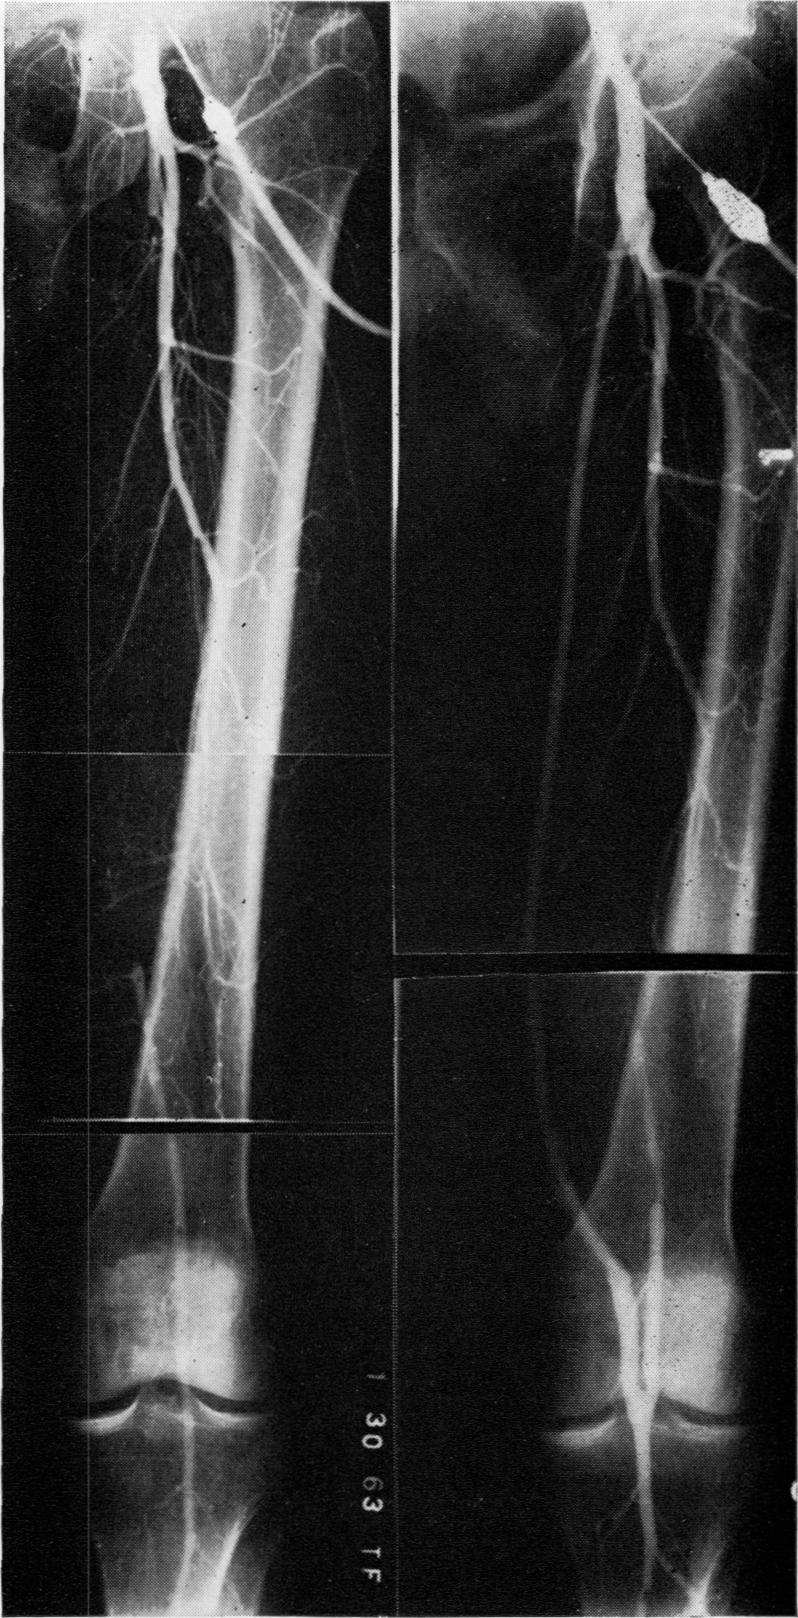

Autogenous venous bypass grafts five years later.

Ann Surg. 1971 Sep;174(3):346-56. doi: 10.1097/00000658-197109000-00003.